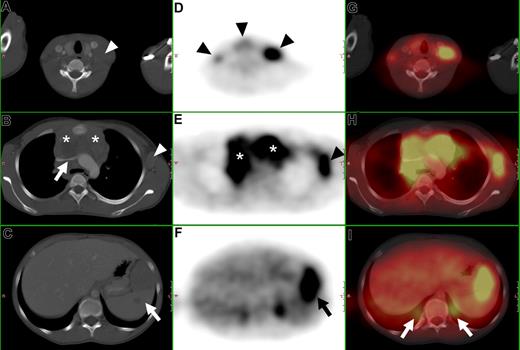

Determination of nodal involvement is based on size criteria. Lymph nodes with a short-axis diameter greater than 10 mm are generally considered positive. Furthermore, clustering of normal-sized but prominent lymph nodes in the anterior mediastinum and the mesentery is suspicious for disease. The use of intravenous contrast medium is not helpful in differentiating normal from malignant lymph nodes. General criteria for extranodal involvement are organomegaly, abnormal mass or structural changes in a normal-sized organ, and abnormal contrast enhancement (Figures 1A-C).16

CT, FDG-PET, and FDG-PET/CT fusion of a 13-year-old female with Hodgkin disease. (A-C) Axial CT images show (A) a cervical lymph node mass (

), (B) a large mediastinal mass (*) compressing the left brachiocephalic vein (

), an enlarged axillary lymph node (

), and (C) an enlarged inhomogeneous spleen (419). (D-F) Axial PET images show pathologic FDG uptake in (D) cervical lymph nodes (

), (E) in the mediastinum (*), in a left axillary lymph node mass (

), and (F) in the spleen (

). (G-I) Fused PET/CT images. (I) Note the misregistration of normal renal FDG excretion (

).

Any focus of visually elevated FDG uptake relative to the background, not located in areas of physiologically increased uptake or where the clinical data do not suggest the presence of a nonmalignant hypermetabolic lesion, is regarded as positive for malignant lymphoma. In organs with physiologic FDG uptake (eg, spleen and liver), focal or inhomogeneous uptake patterns are considered to be indicative of malignant lymphoma (Figure 1D-F). Cut-off values for semiquantitative evaluation (measurement of standardized uptake values) of suspected foci have not been reported yet in the literature, to our knowledge.

Fused FDG-PET/CT images are interpreted using a combination of the criteria as described for CT and FDG-PET alone (Figure 1G-I).